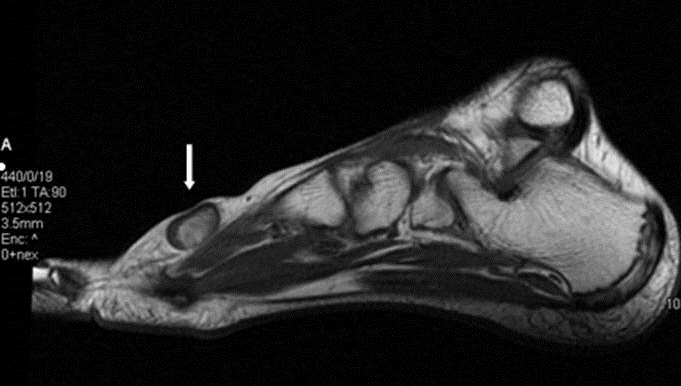

Figura 3. Presenza di flusso in parete. � stata effettuata una RMN con contrasto con acquisizioni multiplanari T1 e T2 pesate anche con tecnica di soppressione del grasso, con il rilievo di una formazione ovalare di 16 x 12 x 20 mm a margini regolari con iperintensit� di segnale centrale nelle pesate T1 e T2 dipendenti, e componente periferica sottile che subisce enhancement contrastografico, in apparente continuit� anatomica con struttura vascolare del fascio vascolo-nervoso dorsale, ascrivibile, in primis, a formazione vascolare o patologia vascolare dilatativa trombizzata (Figure 4, 5 e 6). ![]() |

Figura 5.Scansione sagittale T1 pesata SE. |

Figura 6.Ricostruzione MIP. In questa breve sequenza di immagini si pu� notare il passaggio dal lume vascolare normale alla porzione ectasica e quindi di nuovo al calibro regolare (Figura 7). ![]() ![]() ![]() ![]() ![]() ![]() |